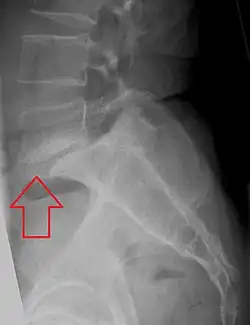

| X-ray of the lateral lumbar spine with a grade III anterolisthesis at the L5-S1 level | |

Spondylolisthesis is graded based upon the degree of slippage of one vertebral body relative to the subsequent adjacent vertebral body.[6] Spondylolisthesis is classified as one of the six major etiologies: degenerative, traumatic, dysplastic, isthmic, pathologic, or post-surgical.[7] Spondylolisthesis most commonly occurs in the lumbar spine, primarily at the L5-S1 level, with the L5 vertebral body anteriorly translating over the S1 vertebral body.[7]

Classification by degree of the slippage, as measured as percentage of the width of the vertebral body:[17] Grade I spondylolisthesis accounts for approximately 75% of all cases.[7]

- Grade III: 50–75%